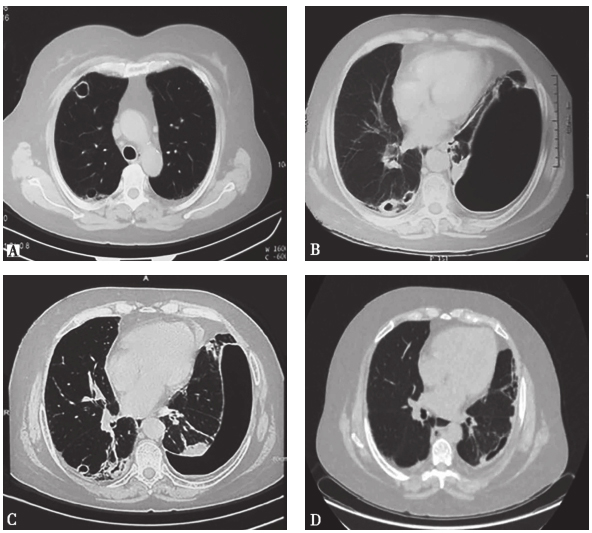

患者1年多前查胸部CT提示肺间质纤维化和肺部空洞(图1A),查G试验、GM试验、痰培养及降钙素原均无异常,未经特殊治疗。9个多月前患者于咳嗽后突发胸闷,于外院查胸部CT提示左肺气胸、右肺空洞,给予头孢哌酮舒巴坦、氟康唑后复查CT空洞变化不明显,气胸较前有所吸收。3个月前,患者着凉后出现咳嗽、咳痰及胸闷,胸部CT提示左侧大量气胸、右肺部空洞(图1B),于外院住院行胸腔闭式引流术后肺部复张。

图1 患者胸部CT影像

A:2009年12月8日胸部CT提示肺间质纤维化、肺部空洞;

B:2010年10月12日胸部CT提示大量气胸、肺部空洞;

C:2011年1月25日左肺野外带可见条片状透亮区及置管影,相邻肺组织密度增高,可见多发条索影,右肺中、下叶可见数个薄壁空洞,部分可见液平,周围可见斑片影,胸膜下分布,左侧胸腔可见少量积液,双侧胸膜增厚;

D:2015年6月11日双肺多发条索影、小条片影,局部胸膜下呈网格样、蜂窝影,右肺胸膜下可见结节影,与胸膜粘连,双侧胸膜增厚,局部包裹气体影,气管及左右支气管开口通畅

胸部CT:双肺纹理增重,左肺野外带可见条片状透亮区及置管影。相邻肺组织密度增高,可见多发条索影。右肺中、下叶可见数个薄壁空洞,部分可见液平,周围可见斑片影,胸膜下分布。气管及其分支通畅,纵隔内未见明显肿大淋巴结,肺动脉主干不宽,心影不大,左侧胸腔可见少量积液,双侧胸膜增厚(图1C)。

该患者出院后门诊随访5年,规律应用小剂量激素(激素逐渐减量,后7.5mg qd维持)、羟氯喹、来氟米特和贝前列素钠等药物,并于2011年4月开始加用环磷酰胺(CTX)200mg q2w输液治疗,并逐渐加量至400mg q2w,后因为皮肤(多于手指及足部)反复破溃,CTX增至600mg q2w,患者皮肤新发溃疡逐渐减少,肺部空洞较前吸收(图1D)。但在CTX减量过程中又出现肢端新发溃疡增加,CTX用量波动于400~600mg q2~3w之间,规律应用至2016年6月。至今病情基本稳定,关节情况稳定,肢端溃疡偶有新发,肺部无新发病变。